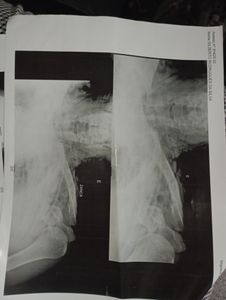

Geralmente para ganhar um pouco a mais faz algumas viagens, foi solicitada uma viagem para silveirânia à noite e logo na entrada da roça o assalto foi realizado pelos passageiros com a tentativa de homicídio. Foram três tiros na cabeça porém a arma mascou, ele aproveitou a situação e saiu correndo desnorteado no escuro e conseguiu chegar na estrada, onde atingiu a lateral da cabine de um caminhão ( o que acabou salvando a sua vida). O motorista do caminhão parou e prestou Socorro, assim como um colega taxista que por coincidência também passava pelo local, Gil continua internado desde o dia do acidente 08/02/2023.

Além dos pontos na cabeça devido a batida na carreta, o impacto fez com que a traquéia dele se compense indo ar subcutâneo para pescoço e peitoral. A perna direita esta imobilizada, e o braço esquerdo, sendo que estão acompanhando a evolução para cirurgia da clavícula, seus pulmões se expandiram devido a água que entrou. Seus dentes tbm foram afetados, deram "um jeito" aqui para amenizar a situação, pois sua boca esta bastante machucada por dentro. Mas posteriormente terá que ir ao dentista e fazer fisioterapia de reabilitação, além de acompanhamento psicológico, ele esta muito abalado.